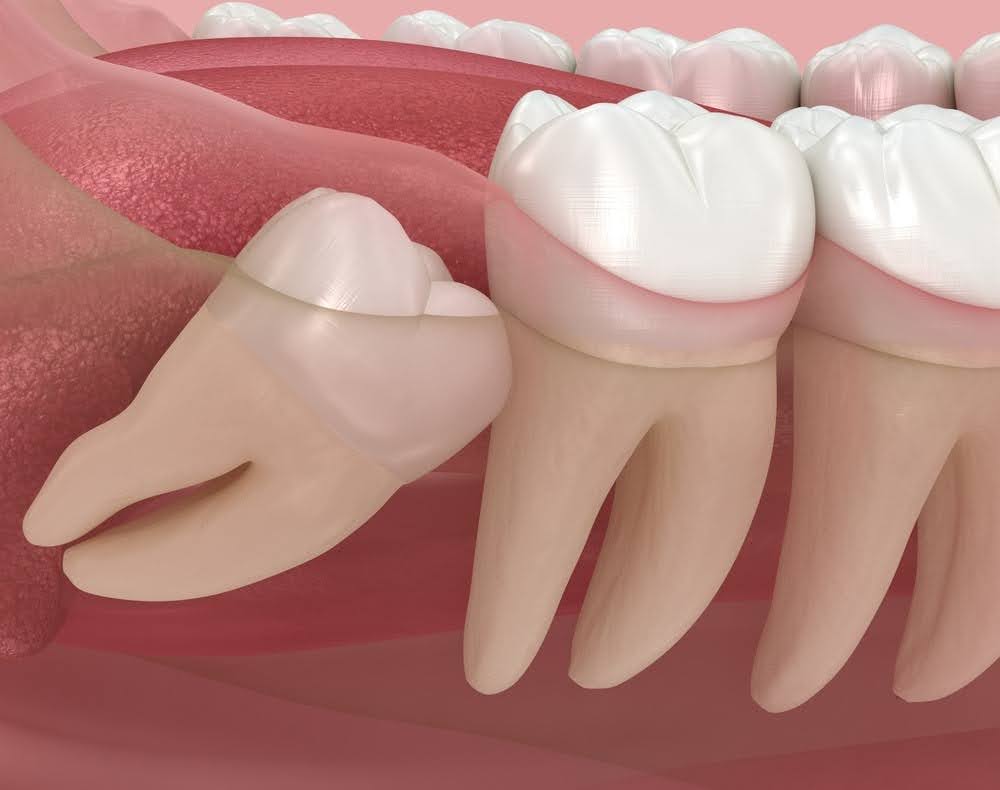

Wisdom teeth are the third set of molars, positioned at the very back of your mouth on the upper and lower arches. They typically erupt between the ages of 17 and 25, which is how they earned the nickname "wisdom teeth."For most people, the jaw simply does not have enough room to accommodate these late arrivals. When wisdom teeth cannot erupt properly, they become impacted, meaning they remain trapped beneath the gum line or emerge at an angle that pushes against neighboring teeth. The results range from mild discomfort to serious infection, cyst formation, and structural damage to adjacent teeth.

- Impaction: The tooth is fully or partially trapped beneath the gum and bone and cannot erupt naturally

- Improper angulation: The tooth is growing at an angle toward the adjacent molar, creating pressure that can damage that tooth's root

- Partial eruption: The tooth has broken through the gum surface partially, creating a flap of tissue where bacteria can accumulate and cause recurring infection

4. Extraction: Dr. Burton gently loosens the tooth from its socket. Impacted teeth may require a small incision in the gum tissue and sectioning of the tooth for safe removal